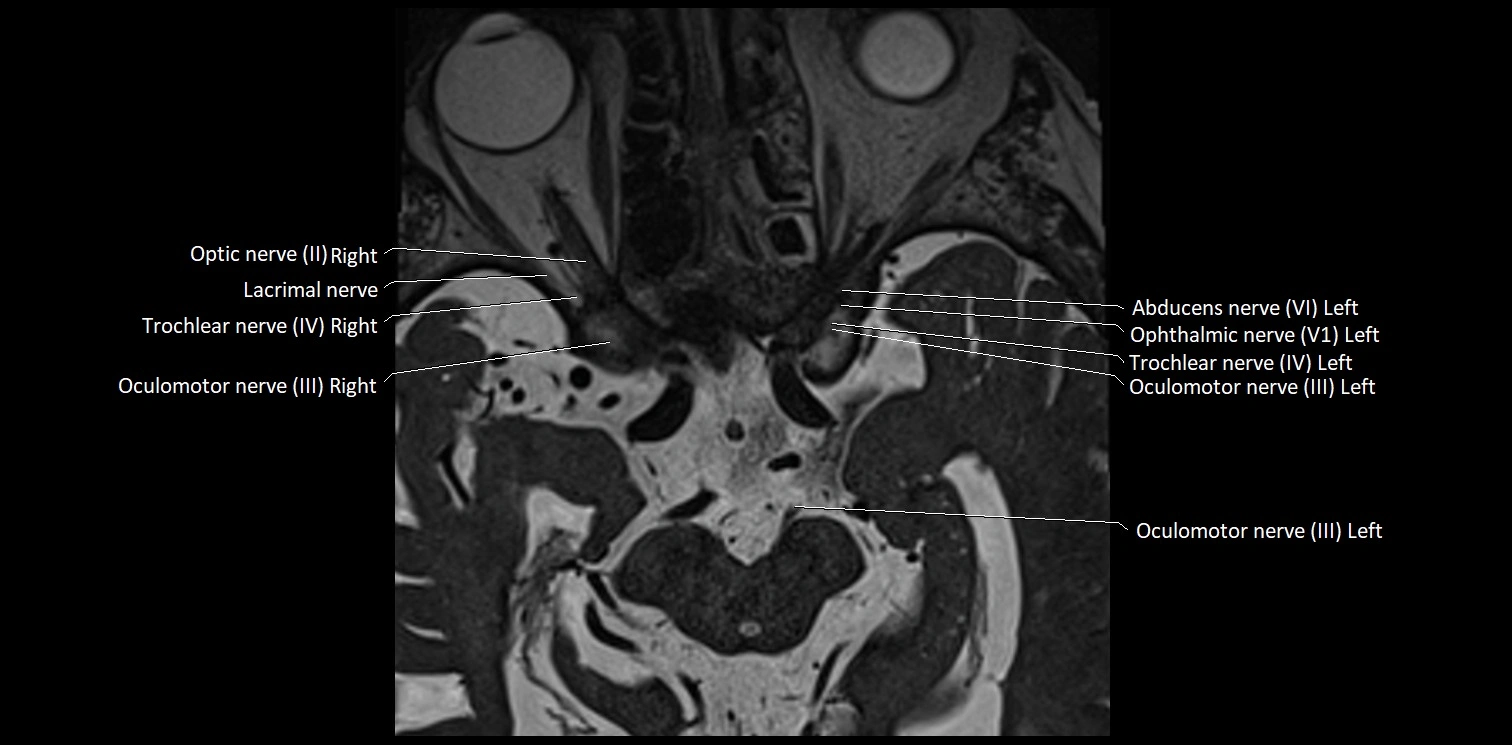

MRI Appearance

• The abducens nerve is a small, thin, linear structure

• Best visualized on high-resolution T2-weighted 3D MRI sequences (e.g., FIESTA or CISS)

• Seen as a hypointense (dark) line running from the brainstem at the pontomedullary junction, traversing the prepontine cistern, and entering Dorello’s canal under the petrosphenoidal ligament, then into the cavernous sinus, and finally the orbit

• May be challenging to visualize in standard MRI due to its small size

• Pathology may be inferred by absence, displacement, or enhancement of the nerve